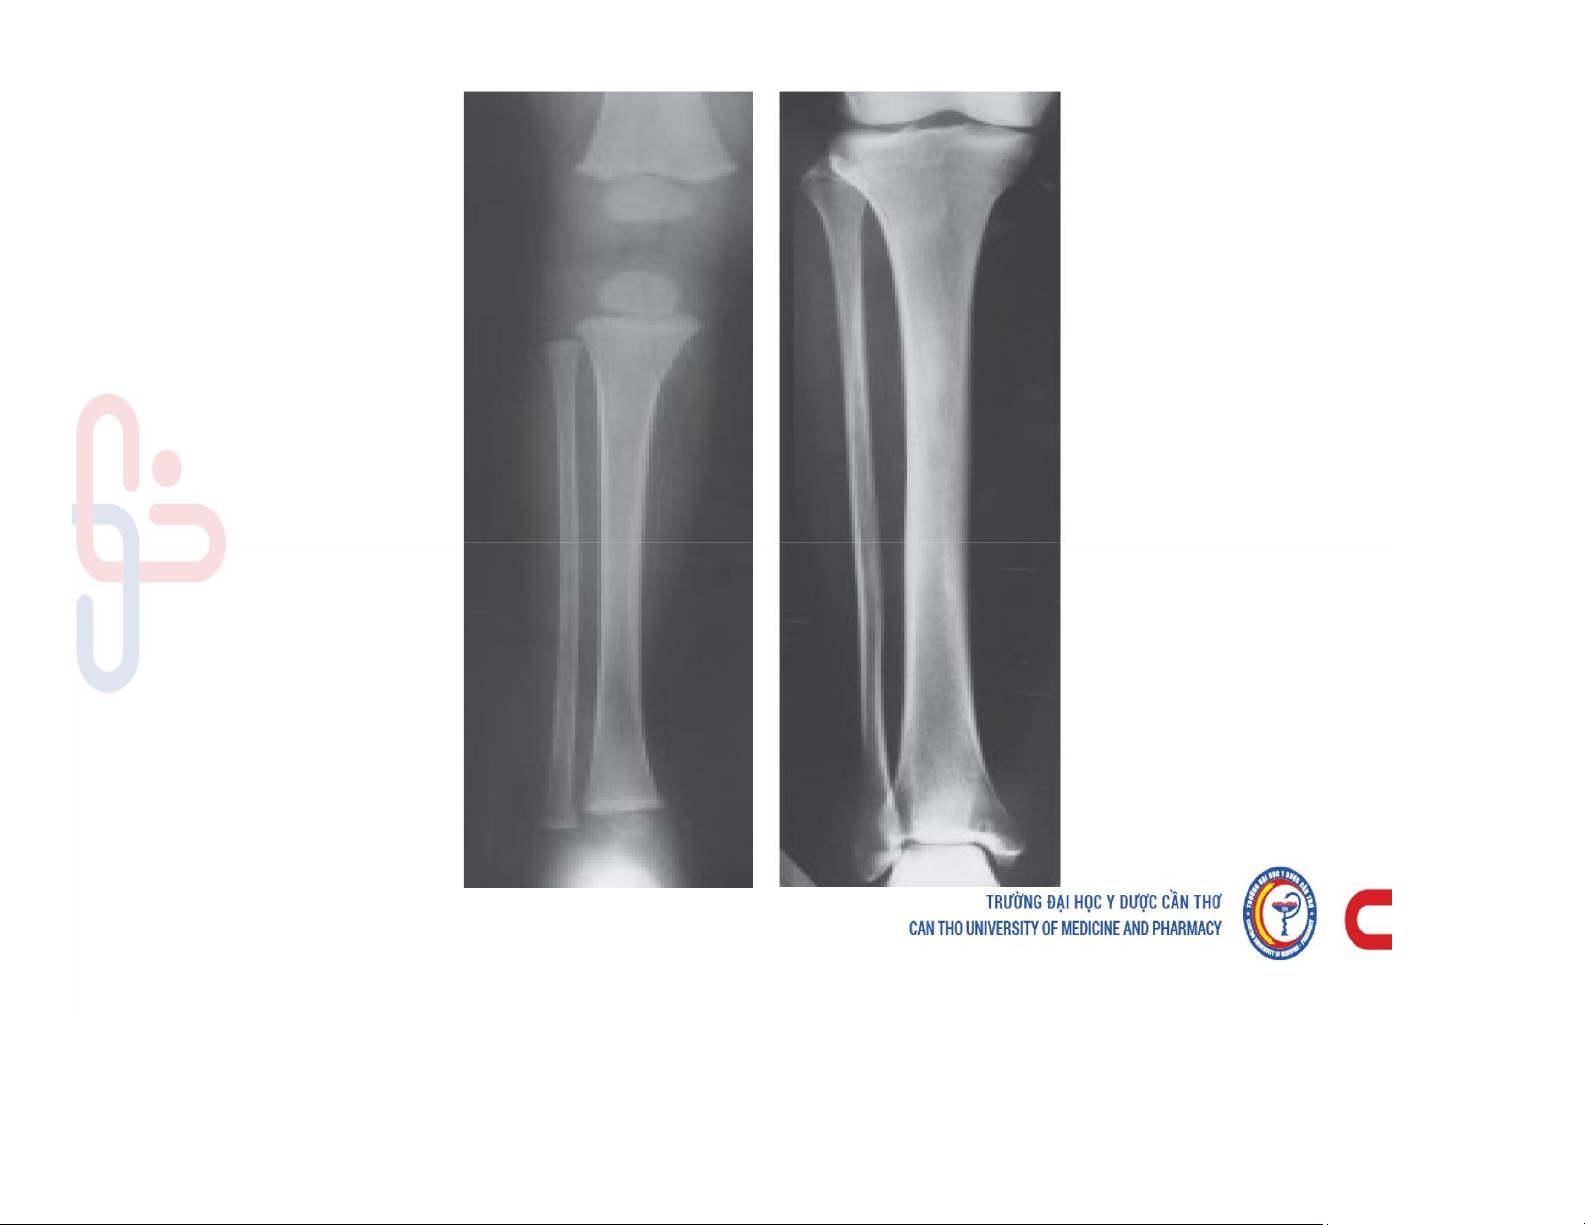

Mô tả và chú thích được các cấu trúc giải phẫu x quang xương khớp. Mô tả các dấu hiệu cơ bản trên phim x quang xương khớp. Phân tích được hình ảnh x quang bệnh lý của một số nhóm bệnh lý xương khớp. Các dấu hiệu cơ bản của phim. Tài liệu giúp bạn tham khảo, ôn tập và đạt kết quả cao. Mời đọc đón xem!